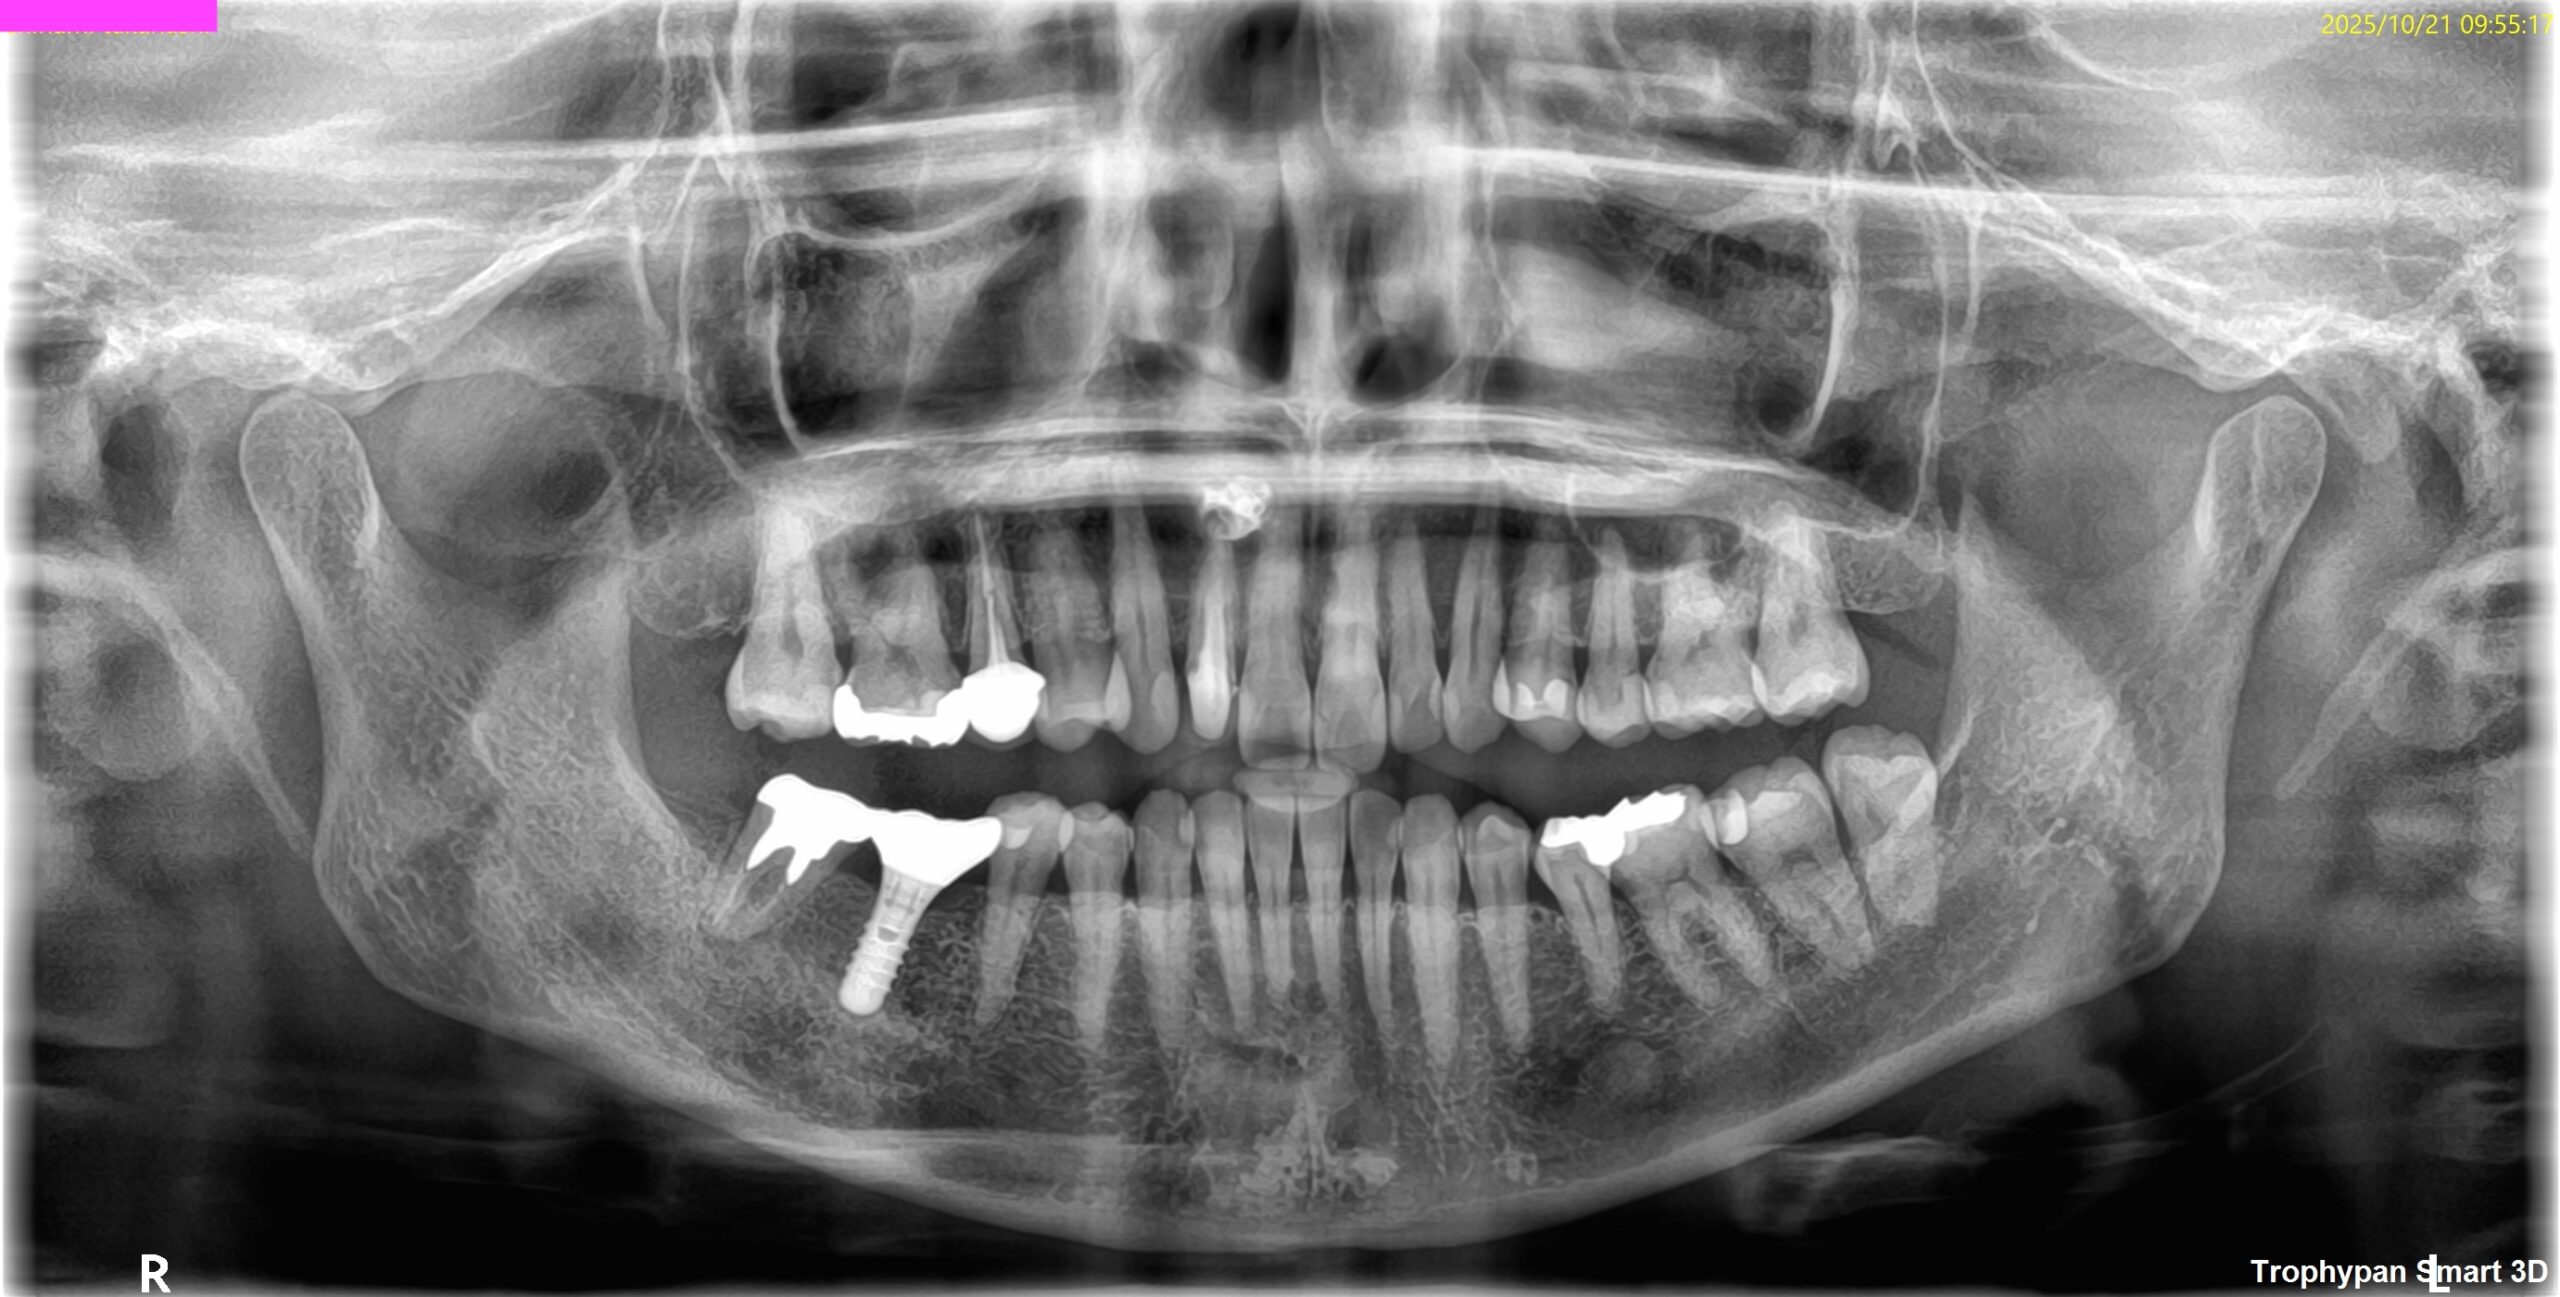

OPG(2025.10.21)

CBCT(2025.10.21)

外科は以下のように行うだろう。

Apexよりも12.5mm下方に#7のApexがあり、そこを3mm切断しようとすれば頬舌的に3.9mの切断が必要だ。

全く難しくはないだろう。